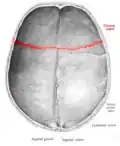

Superior view of anterior part of the skull. Coronal suture runs horizontally. -